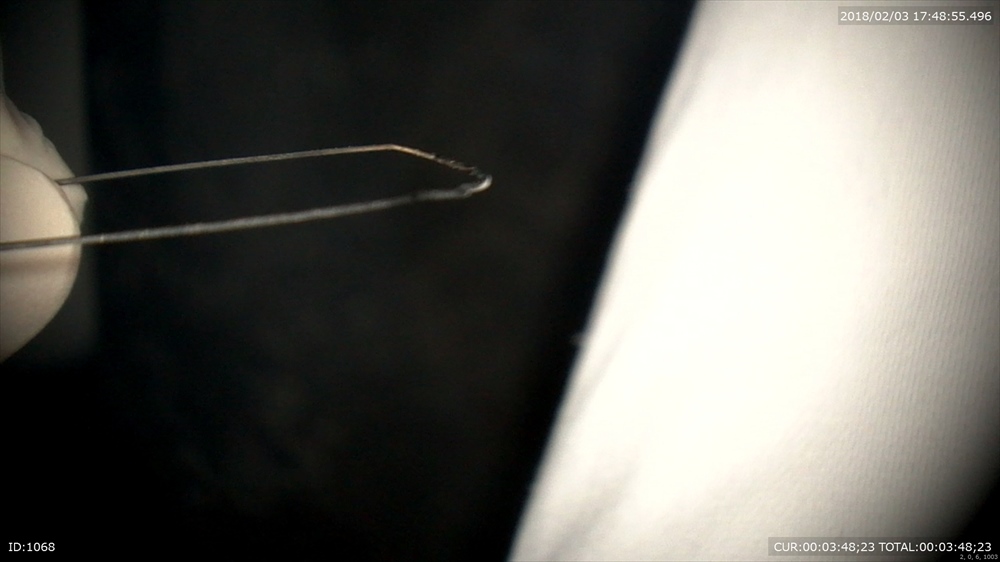

今日最後の患者さまは矯正治療

フィニッシィングステージ

犬歯が甘いので オフセットを。

この様にマイクロスコープを使用して無痛かつ丁寧な治療が当院では可能です。埼玉、八潮、草加、三郷で矯正治療ならBiVi歯科・矯正歯科まで。